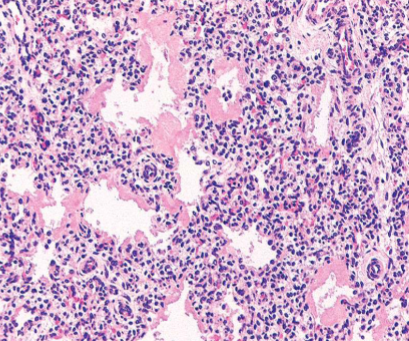

What is the characteristic microscopic lung findings in RDS?

Atelectasis & alveoli poorly developed or collapsed

Hyaline membranes composed of fibrin & cell debris line alveoli

Minimal inflammation

Neonatal Respiratory Distress Syndrome

Eosinophilic thick hyaline membranes line alveoli